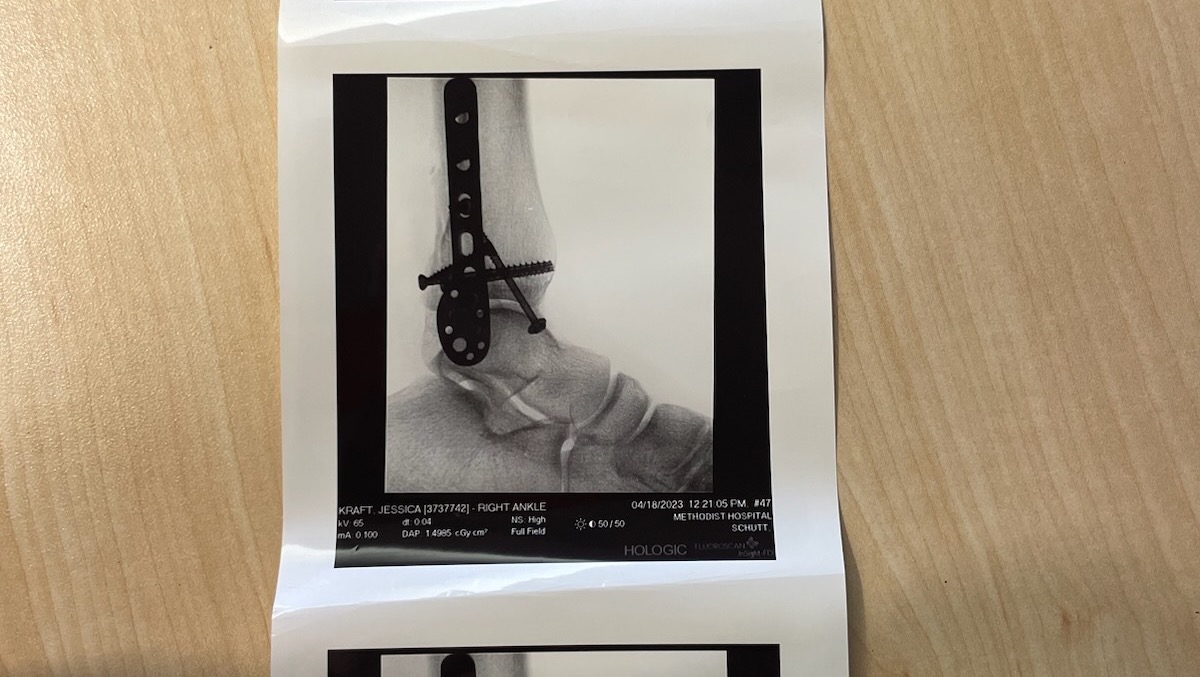

After a night in the emergency room we found out she has a trimalleolar fracture.

Which includes her fibula, tibia, and talus.

So technically all the bones that give your ankle and lower leg mobility.

She will be having surgery tomorrow (4-18-23)